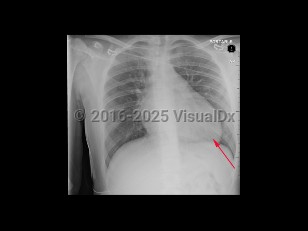

Cardiac tamponadeCardiac tamponade